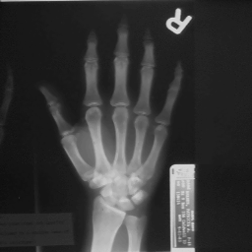

image-369.png image-370.png

Original Hand image Gaussian blur (2.5 pixel radius)

image-371.png image-372.png

Subtracting blur from original Added back to original